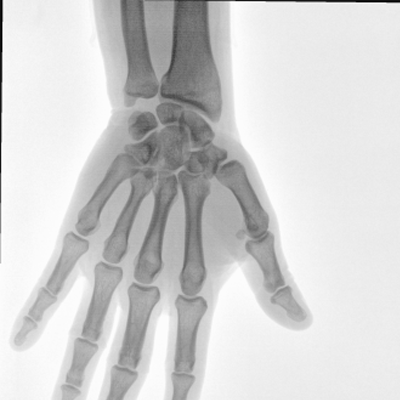

大尺寸動(dòng)態(tài)平板探測(cè)器,高DQE、低噪聲、圖像清晰。采用多分辨率圖像增強(qiáng)處理技術(shù),不同部位不同圖像處理算法,滿足客戶多樣化的需求。

圖形化操控界面設(shè)計(jì):設(shè)有多種人體特征攝影參數(shù),操作簡(jiǎn)便。雙向紅光十字定位系統(tǒng):實(shí)現(xiàn)無射線下的高效定位。信息共享:遵循DICOM3.0格式接口,可無縫對(duì)接云PACS系統(tǒng)。